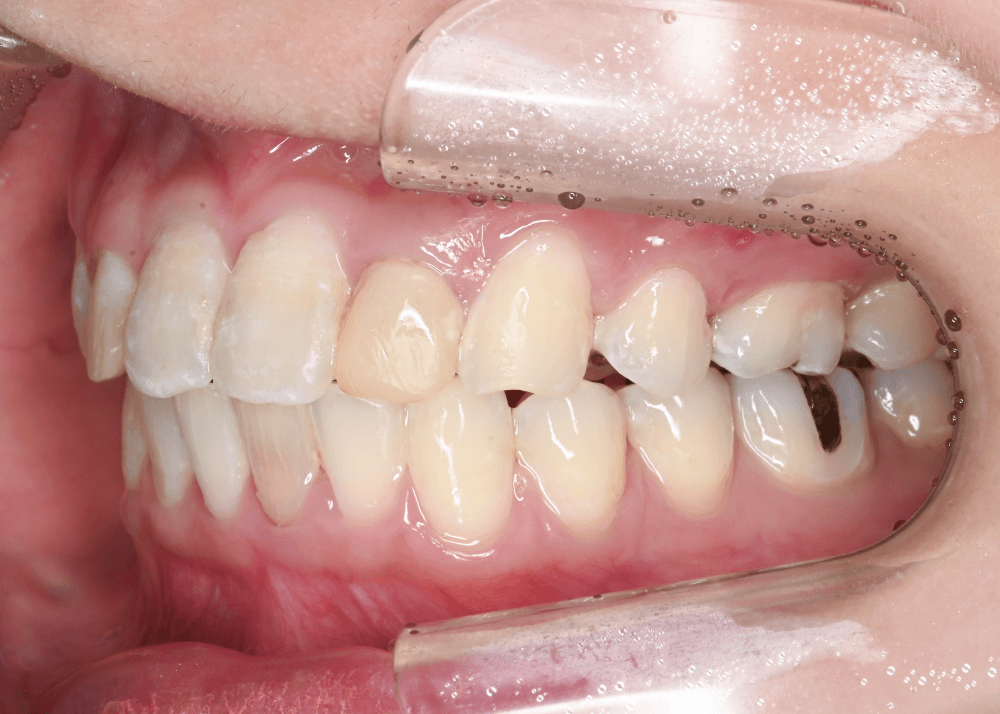

治療前の状態

すでに矯正治療を終えられていたため、歯列に大きなガタつきはなく、上下の歯の咬み合わせも良好でした。

しかし顔貌の観察では以下の特徴が見られました。

側貌(横顔)

上顎前歯が舌側に強く傾斜しており、口唇のサポートが不足していました。

その結果、口元のボリュームが少なく、横顔がやや平坦な印象となっていました。

スマイル時の印象

患者様ご本人も

「笑ったときに歯が奥まって見える」

という違和感を強く感じておられました。

歯並び自体は整っていても、前歯の位置や傾斜によって口元の印象は大きく変化します。

治療前後の写真比較

治療前